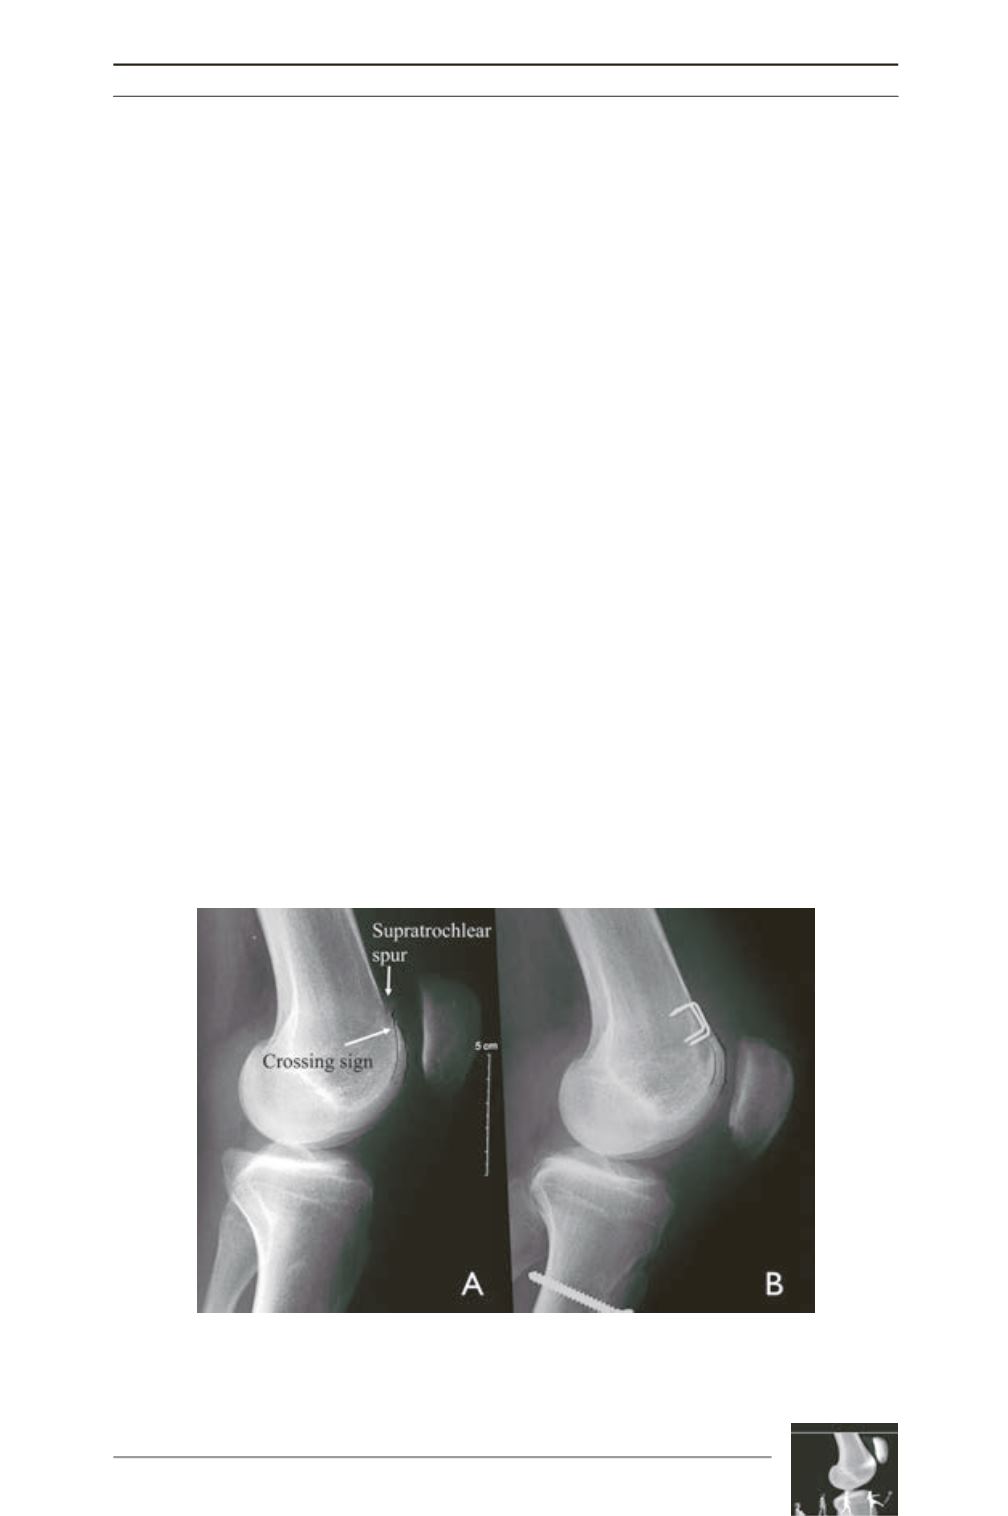

Fig. 5: Example of a (A) pre-operative dysplastic trochlea type B with the

supratrochlear spur and the crossing sign, along with patella alta. (B) The

supratrochlear spur and the crossing sign disappeared after trochleoplasty and the

patella height was corrected with tuberosity osteotomy.